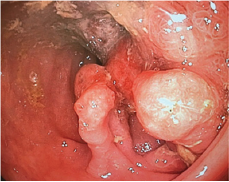

Entering surgery 03/03/2017 colonoscopy is performed (Figure 1) finding mass at the level of descending colon that obstructs 90% of light, continues with exploratory laparotomy finding the tumor mass at the level of descending colon that invaginaba the colon transverse, de-invagination, resection of the tumor mass (Figure 2) and end-colon-terminal anastomosis were performed. It is sent to pathology. Patient with good postoperative evolution, the result of pathology reports as suggestive of Lynch Syndromes, a genetic study is carried out in which Peutz-Jeghers de novo syndrome is reported, which is more compatible with the patient's clinic.

Figure 1: Colonoscopy, courtesy Dr Vasconez